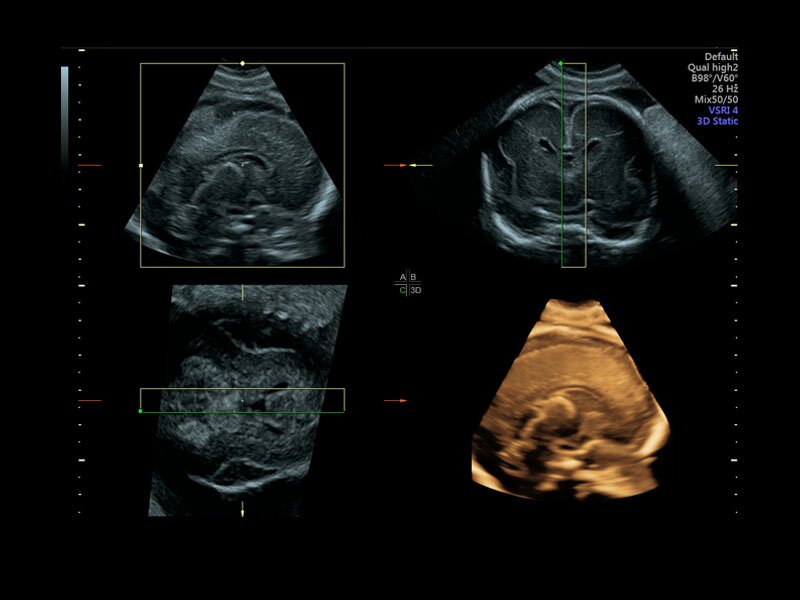

Клинические изображения

• Программа объемной визуализации плода классический HD-Live + расширенный пакет Hdlive Silhouette и Studio:

• HDlive Flow - перемещаемый источник света, совместимый с визуализацией кровотока в 3D

• HDlive Silhouette - режим "Силуэт" с подчеркиванием границ тканей и объектов, "объем в объеме"

• HDlive Flow Silhouette - режим "Силуэт" с выделением границ полостей сердца и сосудов, совместимый с визуализацией кровотока

• HDlive Studio - три независимых источника освещения с регулировкой интенсивности

• Программа 3D и режим инверсии (при наличии специализированных датчиков)

Объемное сканирование Voluson — 3D/4D вашей мечты

Объемное УЗИ на Voluson E10 — это не просто потрясающе красивая картинка, это ценный инструмент получения дополнительной информации при обследовании женщин.

Voluson E10 поддерживает инновационные технологии формирования изображений — HDlive Silhouette и HDlive Flow, которые позволяют увидеть мельчайшие детали. Алгоритм SonoRenderlive упрощает рабочий процесс и дает возможность реконструировать изображение поверхностей, определяя область перехода между тканью и жидкостью.

• HDlive

Инновационная технология визуализации HDlive обеспечивает получение реалистических изображений за счет эффекта объемного зрения, повышая достоверность клинической оценки. Теперь режим HDlive дополняют две новые функции:

• Технология HDlive Silhouette — задает разный уровень прозрачности, помогая выявлять контуры внутренних структур и точнее оценивать состояние плода в первом триместре.

• Технология HDlive Flow — повышает реалистичность визуализации сосудистых структур, улучшая восприятие глубины (по сравнению с традиционным цветовым допплером и функцией HD-Flow).